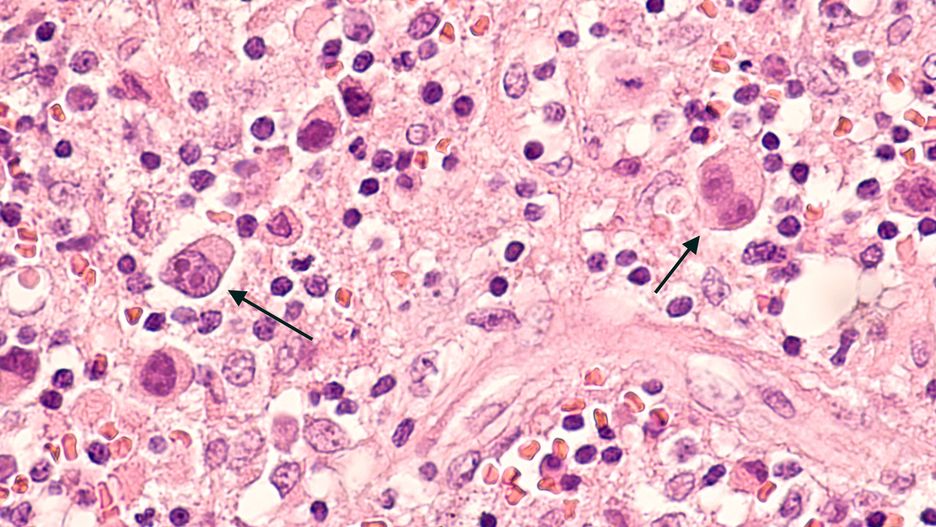

Obraz mikroskopowy węzła chłonnego u pacjenta z chorobą Hodgkina (chłoniaka), przedstawiający dwie komórki Reeda Sternberga w tym samym polu.Obraz mikroskopowy węzła chłonnego u pacjenta z chorobą Hodgkina (chłoniaka), przedstawiający dwie komórki Reeda Sternberga w tym samym polu.